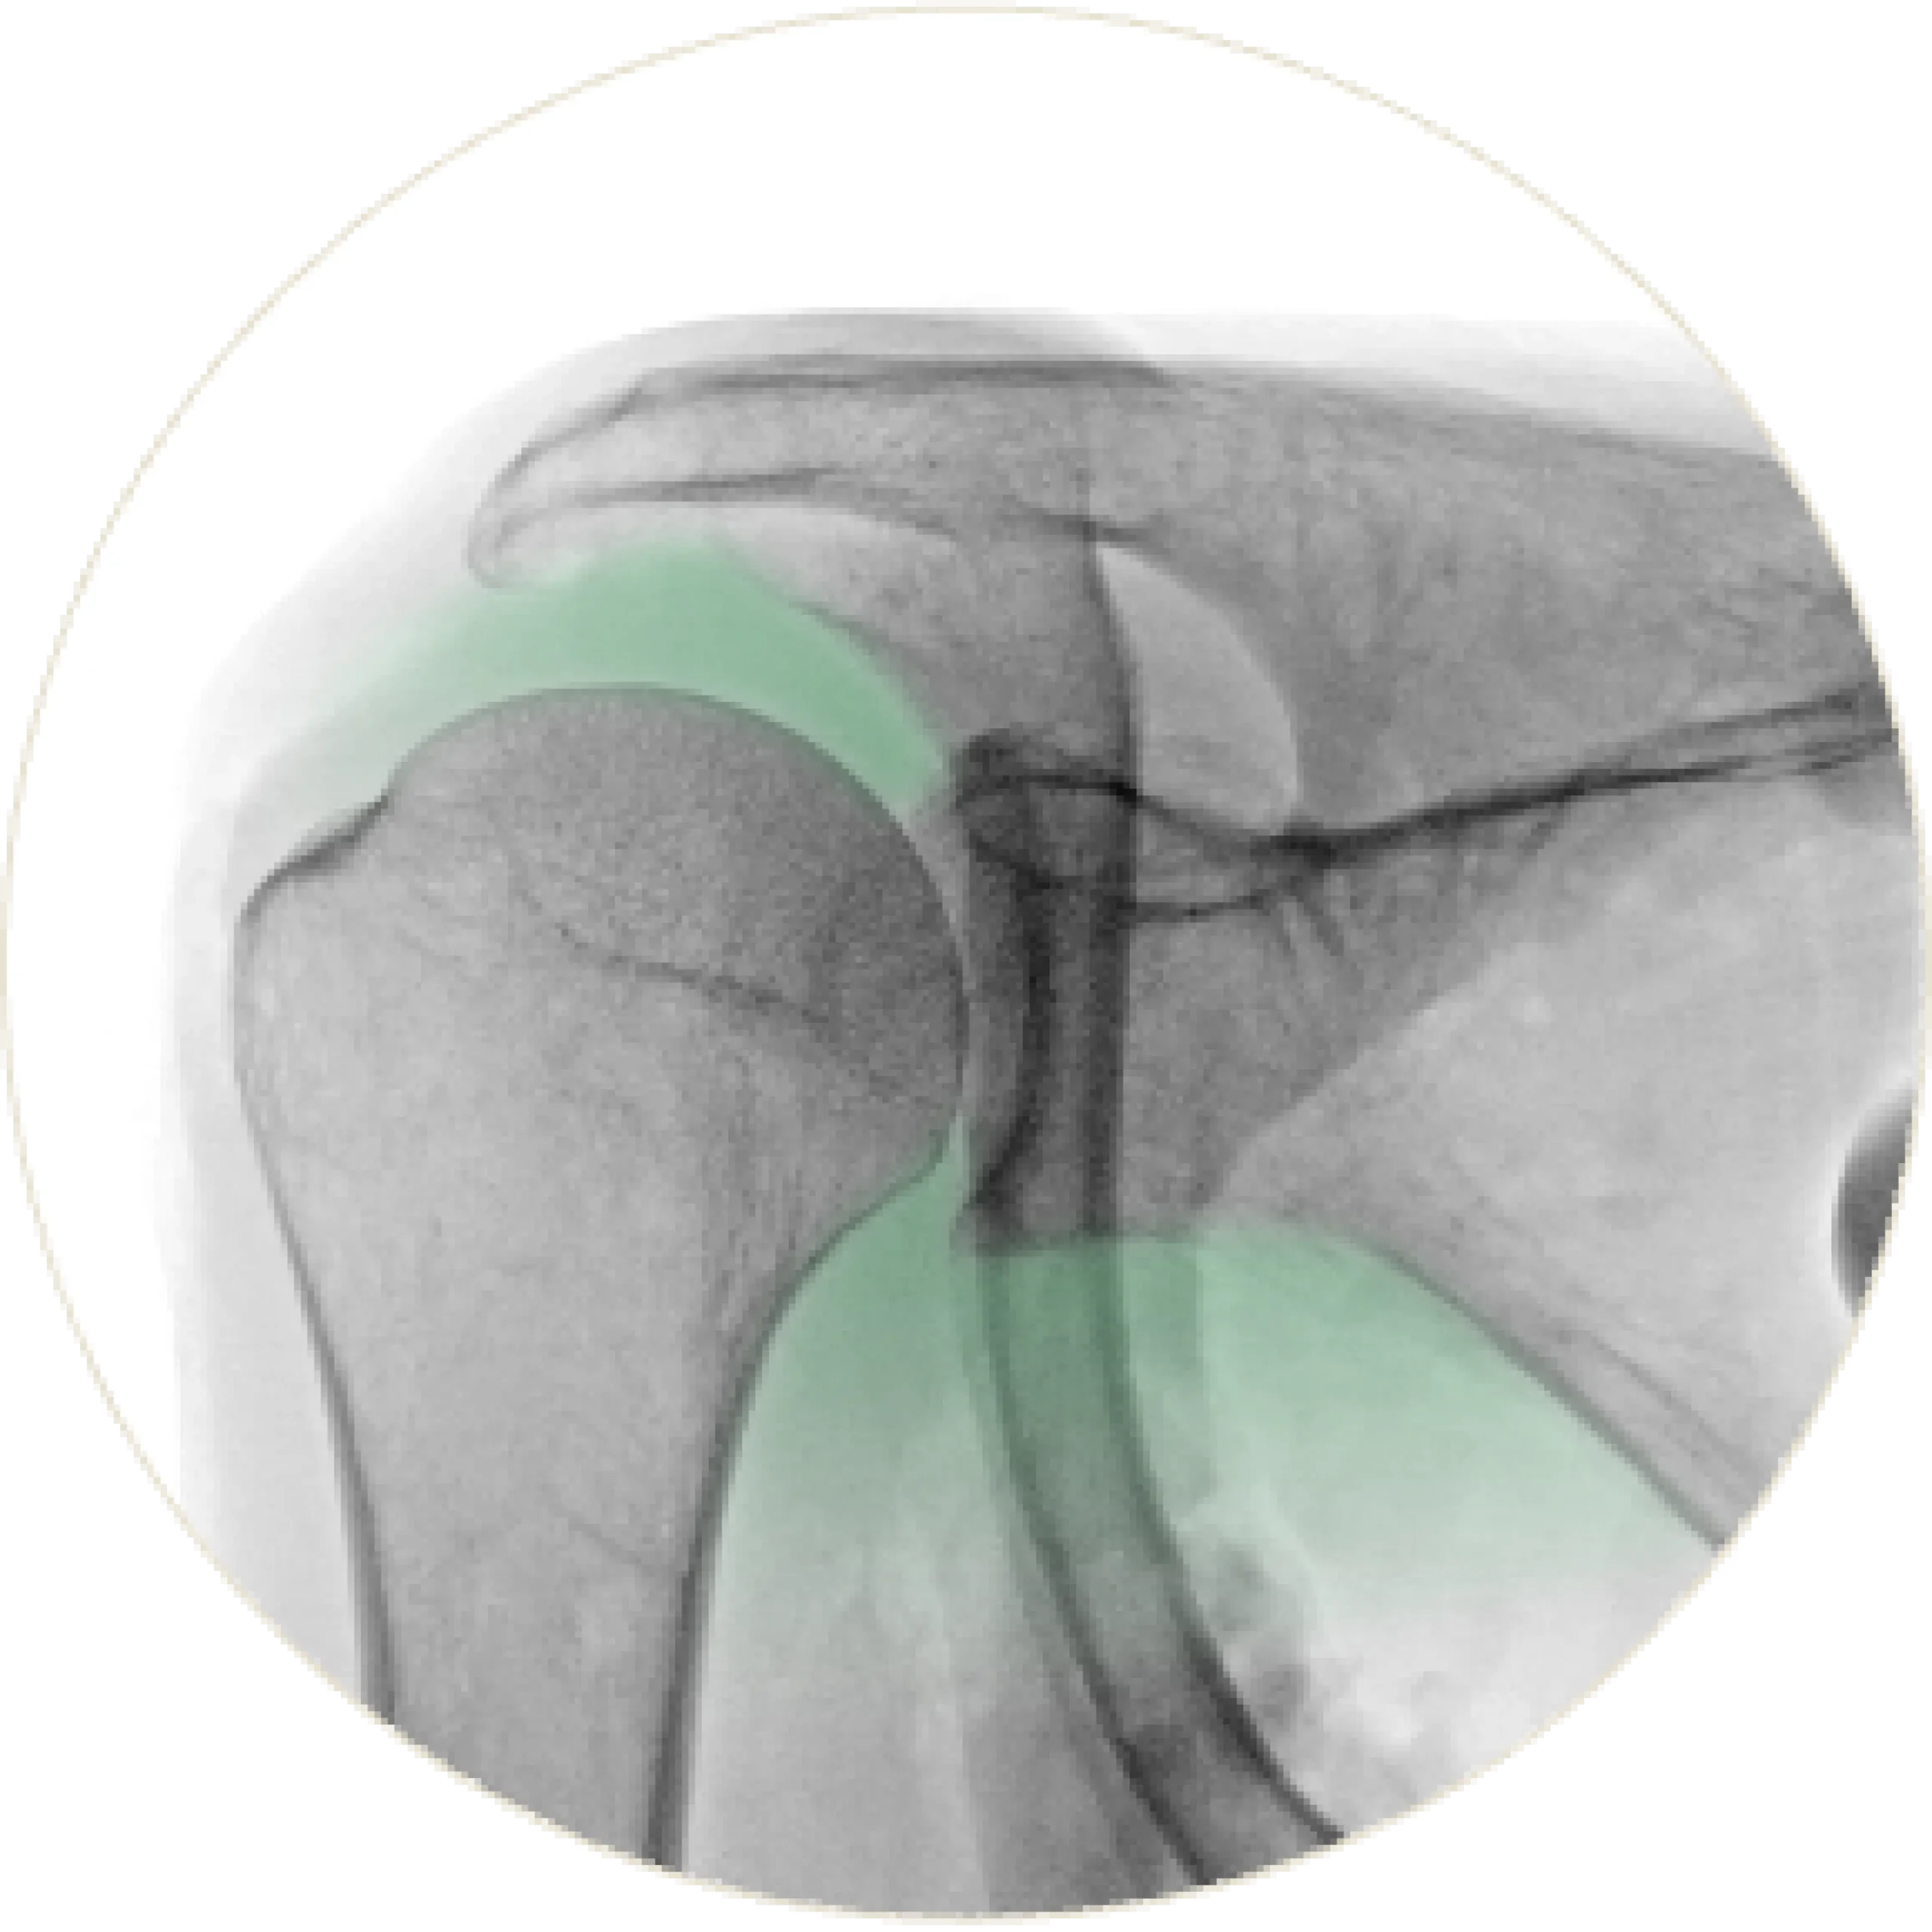

Normal Spacing

A normal glenohumeral joint maintains proper alignment and consistent joint spacing. The humeral head remains centered within the socket, preserving smooth motion and stable shoulder function.